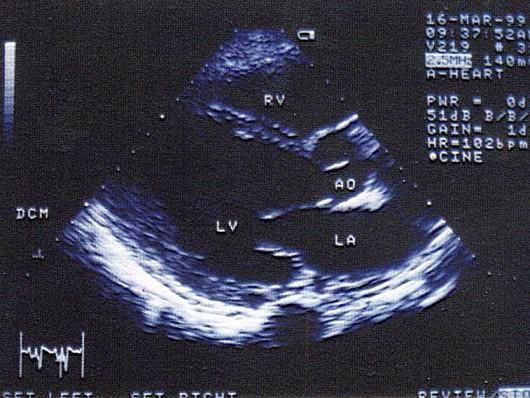

问题 该男,30岁,血压正常范围,心电图正常,T,T正常,该病例最可能的诊断?(?)

选项 A.冠心病 B.高血压心脏病晚期 C.甲状腺功能亢进型心脏病 D.扩张型心肌病 E.肥厚性心肌病

答案 D